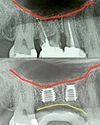

الصور